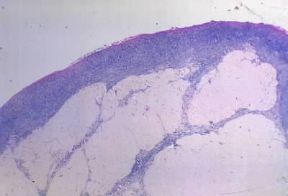

Involuzione . Ovaio senile con assenza di follicoli oofori e presenza dei cosiddetti corpi fibrosi albicali.

De Agostini Picture Library